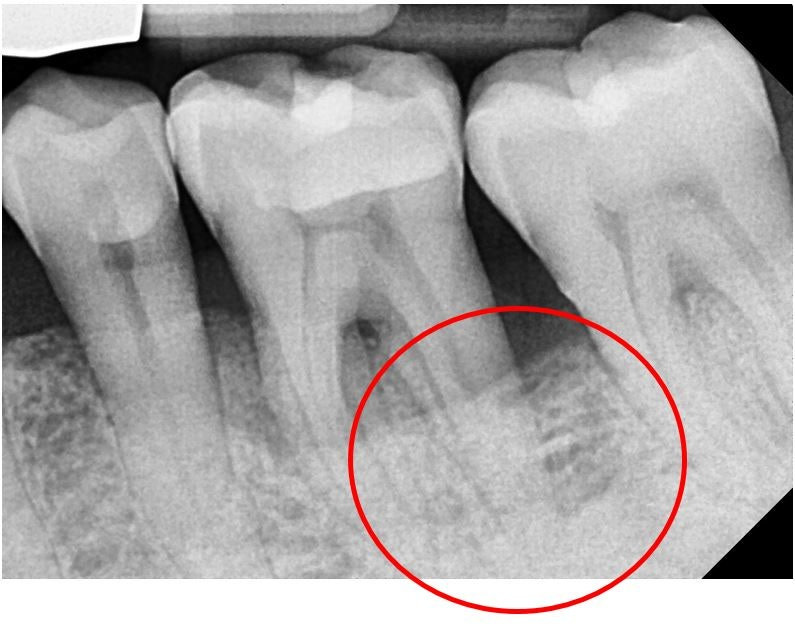

이빨이 흔들리는 증상은 단순 피로 때문이 아니라 치주염, 잇몸 염증, 교합 문제, 치근 손상 등 다양한 원인으로 발생합니다. 방치하면 영구치가 손상되거나 발치까지 이어질 수 있어 초기 대응이 무엇보다 중요합니다.

| 치아가 좌우로 흔들림 | 치주염·치조골 감소 |

- 🦴 치조골 재생치료 — 잇몸뼈 회복

이빨이 흔들린다면 이미 잇몸 뼈나 조직에 문제가 있다는 신호일 수 있습니다. 증상이 가벼워 보여도 꾸준히 진행되면 치료가 어려워지므로 빠른 진단과 치료가 무엇보다 중요합니다. 초기 관리만 잘해도 치아를 충분히 지킬 수 있습니다.